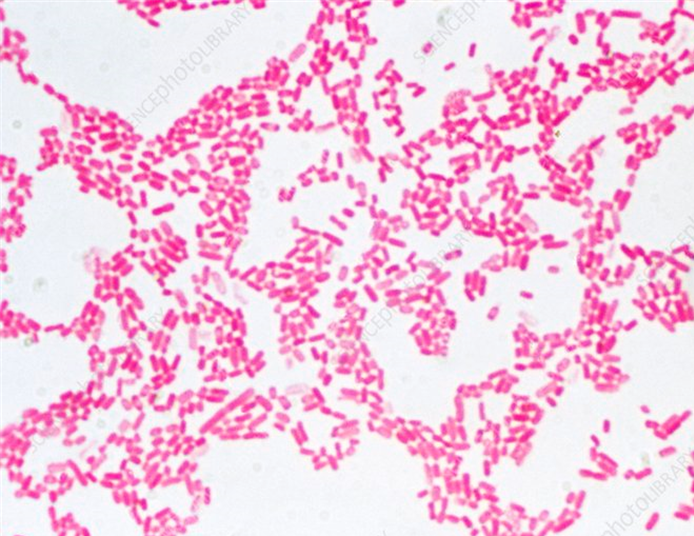

Resultado:

• Bacterias moradas= Gram positivas (+)

• Bacterias rojas= Gram negativas (-)

Se realizó la tinción de Gram de una muestra de pulque y se tomo una micrografía a 100x.

Realiza la descripción

• Debido a la sospecha de contaminación fecal en un agua para el consumo humano, se realizó una tinción de Gram al sedimento de la muestra.

¿Qué microorganismo podría estar asociado?